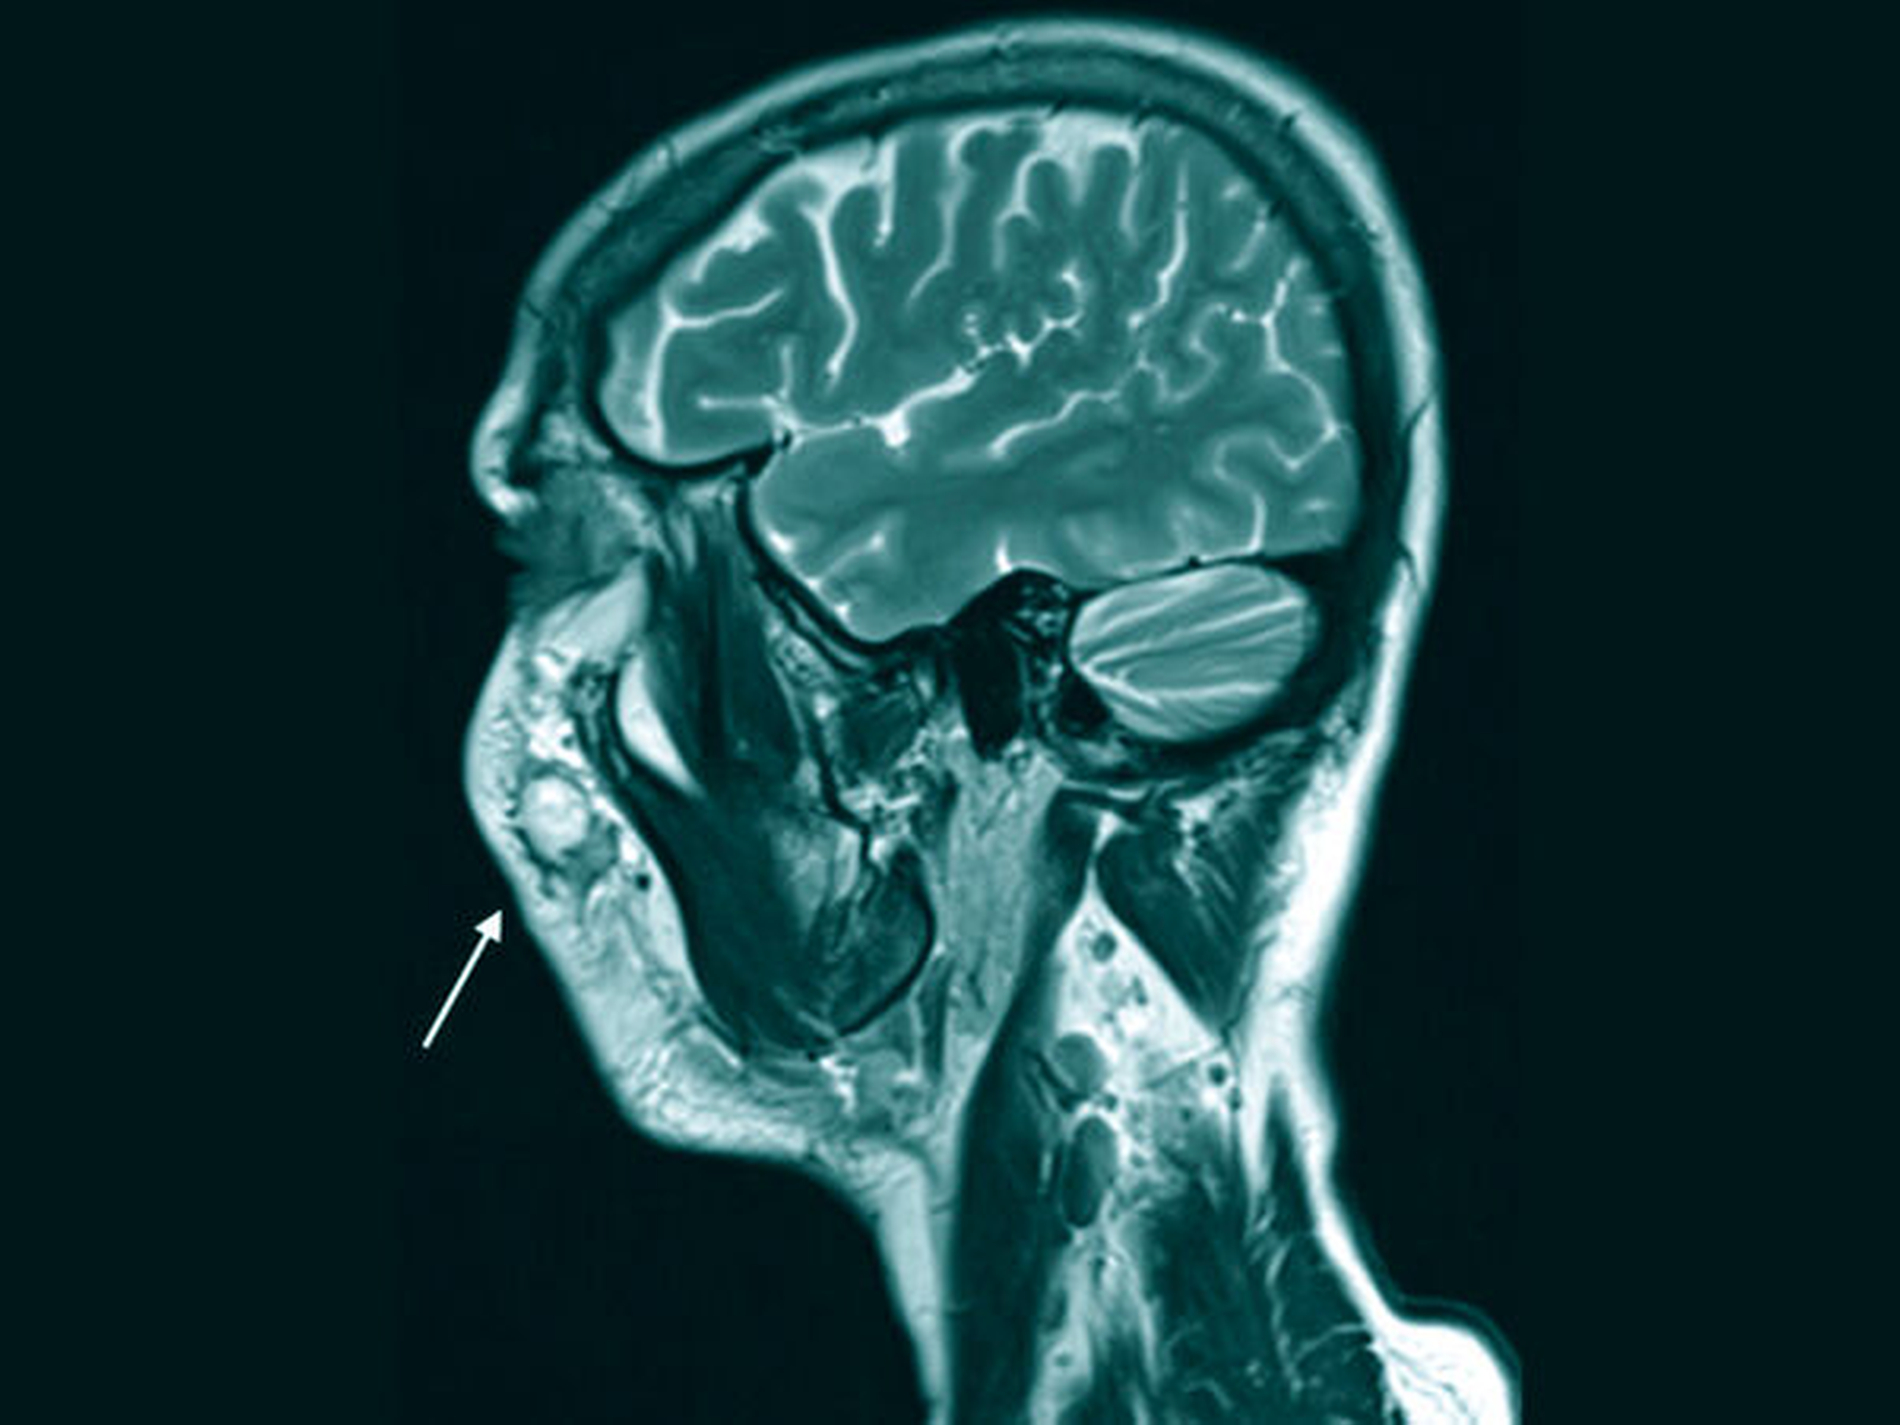

Nach einer Woche zeigte sich der Befund zunächst deutlich regressiv, jedoch nahm die Schwellung nach einer weiteren Woche wieder zu und es kam zu erneutem Eiteraustritt aus der Inzisionswunde. In der mikrobiologischen Diagnostik wurden spärlich Staphylokokken und Streptokokken nachgewiesen, woraufhin wegen der Penicillin-Allergie eine orale Antibiotikatherapie mit Clindamycin 600 mg dreimal täglich begonnen wurde. Zusätzlich wurde aufgrund der Langwierigkeit des Geschehens eine Magnetresonanztomografie (MRT) angefertigt, um eine detaillierte Beurteilung der Weichteile zu ermöglichen. Hierbei kamen mehrere abgekapselte Areale (im Maximum 1,5 cm x 1 cm) zur Darstellung, die prinzipiell mit eingebrachten Fremdkörpern (Filler) beziehungsweise mit Abszessformationen zu vereinbaren waren. Darüber hinaus waren eine diffuse entzündliche Veränderung der rechtsseitigen Wangenweichteile und vergrößerte, am ehesten reaktiv veränderte, zervikale Lymphknoten auffällig.

Falls anhand von Anamnese und Klinik keine eindeutige Diagnose gestellt werden kann, sollte eine weitergehende Bildgebung erfolgen. Hierbei ist im Bereich der Kopf/Hals-Weichteile die Ultraschalldiagnostik das erste Mittel der Wahl, da diese schnell und kostengünstig verfügbar und mit keiner Strahlenbelastung verbunden ist. Nachteil der Sonografie ist, dass diese untersucherabhängig ist und nur bei ausreichender Erfahrung valide Ergebnisse liefert [Kotecha et al., 2008; Schön et al., 2002]. Bei unklaren sonografischen Befunden sollte daher eine Schnittbildgebung durchgeführt werden, zur Weichteildiagnostik empfiehlt sich die MRT. Ein großer Vorteil der MRT liegt darin, die genaue Ausdehnung des Befunds in Bezug auf die Nachbarstrukturen darzustellen – auch im Hinblick auf eine mögliche spätere chirurgische Intervention. Eventuell können in der MRT auch Rückschlüsse auf das eingebrachte Material gezogen werden [Mundada et al., 2017].